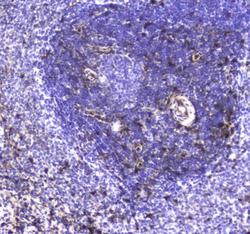

- IHC analysis of S100A10 using anti-S100A10 antibody (A02787-2). S100A10 was detected in paraffin-embedded section of human lung cancer tissue. Heat mediated antigen retrieval was performed in citrate buffer (pH6, epitope retrieval solution) for 20 mins. The tissue section was blocked with 10% goat serum. The tissue section was then incubated with 1μg/ml rabbit anti-S100A10 Antibody (A02787-2) overnight at 4°C. Biotinylated goat anti-rabbit IgG was used as secondary antibody and incubated for 30 minutes at 37°C. The tissue section was developed using Strepavidin-Biotin-Complex (SABC)(Catalog # SA1022) with DAB as the chromogen.